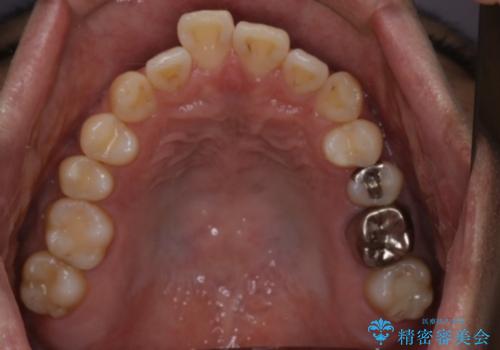

- 前歯の出ているのが気になる、下唇を噛んで痛いとのことで来院された患者様です。マウスピース矯正をご希望でした。

奥歯の噛み合わせはしっかりしていましたので、奥歯の動きは最小限にし、前歯の並びに集中した治療計画+インビザラインのシミュレーションを作成しました。

奥歯の噛み合わせは整っていたため、前歯の並びを美しく修正することに専念できました。マウスピース矯正による治療で短期間で改善しました。